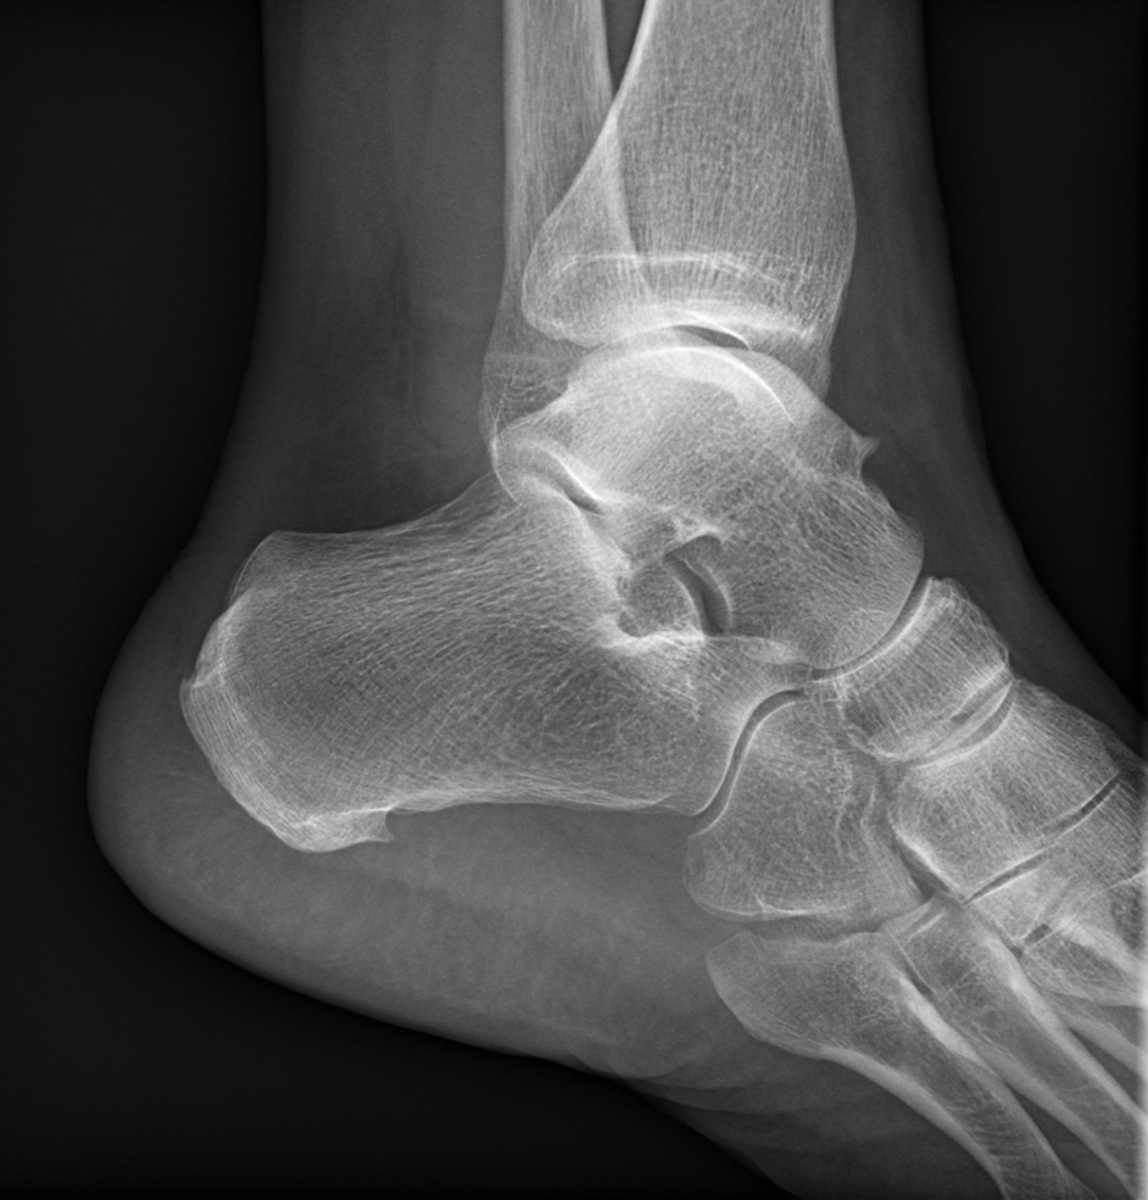

Ukázky RTG snímků